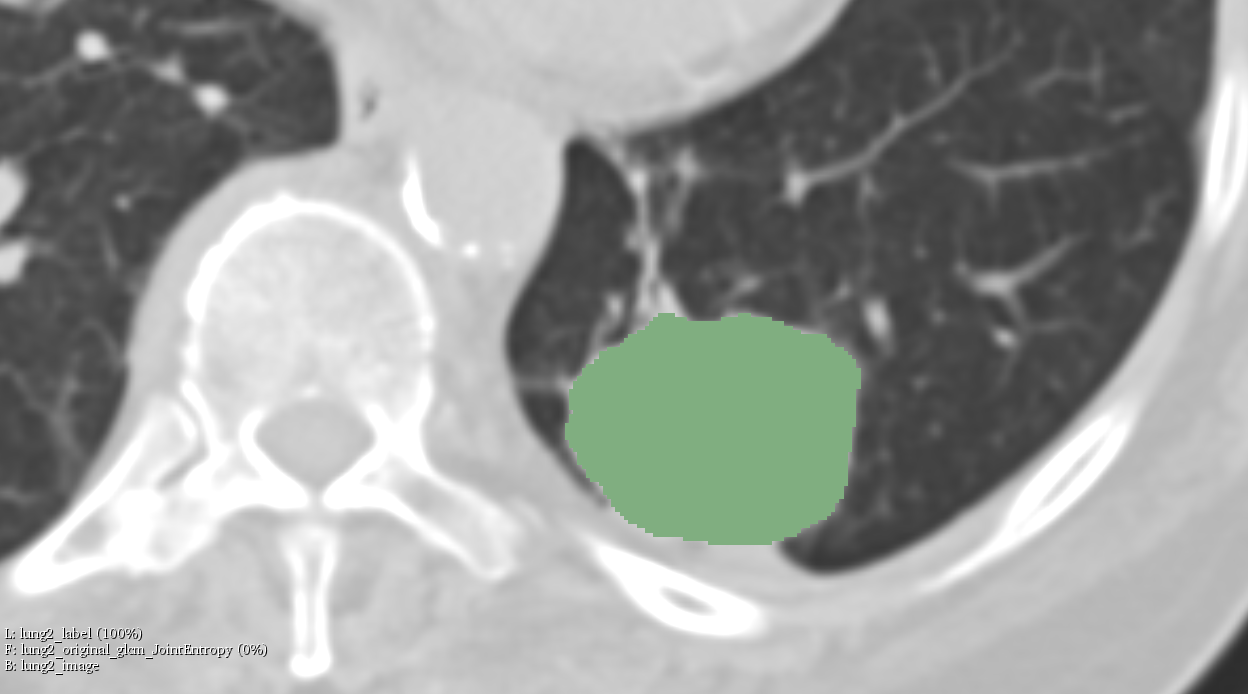

Illustrations

Objective #2